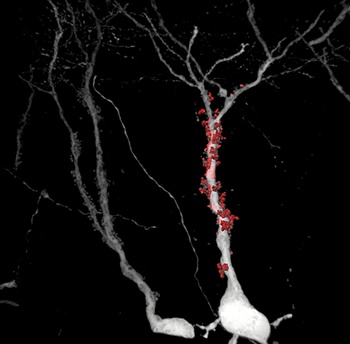

Obrázek 1.: Data s vysokým poměrem S/N dosaženým pomocí virového (rebies) vektoru umožníla vědcům přesné rekonstrukce těchto struktur ve 3D - části specifických synapsí.

Neurony jsou označeny virovým vektorem, který se v buňkách exprimuje jako intenzivní fluorescenční protein, ten poté vyplní veškeré neuronové výběžky včetně velmi dlouhých axonů. Takto připravené vzorky jsou snímány pomocí konfokálního mikroskopu a posléze analyzovány. Pomocí dedikovaného softwaru je vytvořen 3D model celých dendritů, dendritických trnů a synapsí. Tyto modely jsou posléze použity pro kvantifikaci klíčových anatomických parametrů.